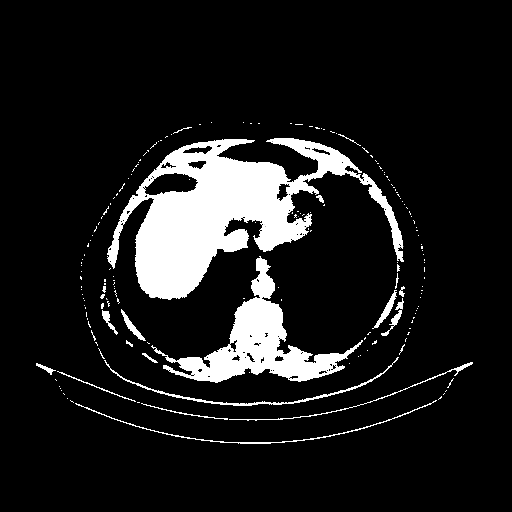

Original VENOUS CT scan

Full window (WL 1023.5, WW 4095 β†’ Low βˆ’1024, High +3071)

Actual HU range: [-1024.0, 3071.0]